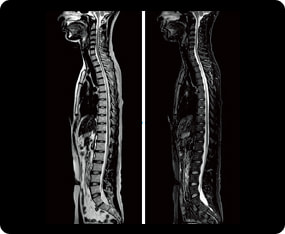

頭部MRI検査の症例画像

脊髄